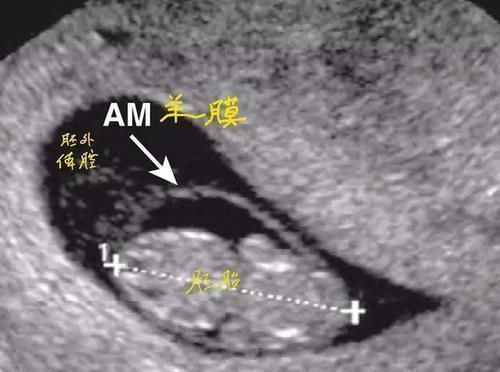

而这层保护罩其实就是羊膜,它可以起到保护小婴儿的作用。

我们可以把羊膜比喻成摇篮,胎宝宝被羊膜包裹就像在摇篮中发育一样,而羊膜可以使宝宝周围的温度保持恒温,可以保证更多的氧气能帮助宝宝更好的呼吸。如果宝宝带着羊膜出生,那么便能更快地接受外界环境。

婴儿被羊膜包裹其实就相当于多了一个保护层,一旦羊膜破了,那么羊水就会流出。相信怀孕过的女性都知道,一旦羊水破了其实是很严重的,轻则会导致流产,因此它的另外一个作用就是为了保护胎儿。